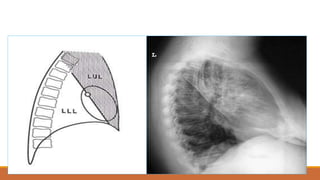

Các thùy phổi

Các thùy phổi -Phổi (P): Thùy trên, giữa và dưới - Phổi (T): thùy trên và dưới